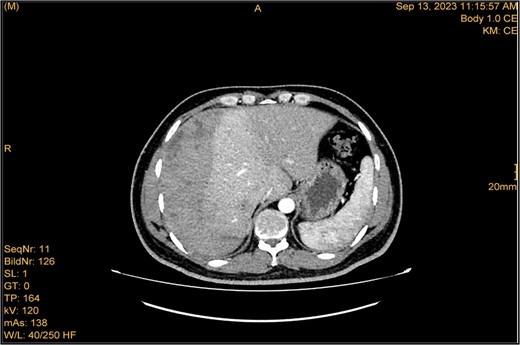

A 41-year-old male with a clear medical background, presented to the Emergency Department with right upper quadrant (RUQ) abdominal pain for two days, associated with fatty dyspepsia, anorexia, nausea, and vomiting. On arrival, his heart rate was 111 bpm with a blood pressure of 128/94 mmHg. On examination, a yellowish discoloration of skin and sclera was noted with a negative murphy sign. Investigations showed elevated liver enzymes (LFT). An initial abdominal ultrasound showed a distended gallbladder with a thickened wall and multiple stones, largest measuring approximately 1.4 cm, and a common bile duct measuring 5 mm (Fig. 1). A magnetic resonance cholangiopancreatography (MRCP) identified a tiny 4-mm mid-cystic duct stone without intrahepatic biliary dilatation. After the initial management, an emergency LC was performed, which posed minimal challenges. Fortunately, no intraoperative complications were reported. A drain was kept in the subhepatic area, and the patient was kept under close observation. Second day postoperatively, the patient experienced dizziness and an intense RUQ pain despite proper analgesia. His heart rate was 89 bpm with a blood pressure of 107/64 mmHg. Investigations showed a drop in hemoglobin level from 13.8 to 9.9 g/dl. An abdominal ultrasound showed a right subcapsular heterogeneous collection with a scalloped liver surface (Fig. 2). Therefore, an initial diagnosis of ISH post-LC was considered. Following the initial fluid resuscitation and blood transfusion, a further decline in hemoglobin level was noted reaching 8.8 g/dl. Further blood transfusion was commenced achieving stabilization. Further CT scan showed subcapsular hepatic hematoma measuring 7.1 × 19 × 21 cm, in its transverse, anteroposterior, and craniocaudal diameters, respectively, with no evidence of active extravasation (Fig. 3) confirming the final diagnosis of ISH post-LC. A multidisciplinary decision was made to continue conservative management after a proper explanation of the potential risk of sudden rupture of hematoma. The patient’s clinical condition and hemoglobin level, in addition to drain output, were meticulously monitored in the general ward, ensuring early detection of deterioration. Four days later, a follow-up CT scan revealed no new significant interval changes (Fig. 4). Nine days postoperatively, the patient was discharged with a follow-up appointment, which showed almost complete resolution.

Enhanced CT scan utilizing bleeding protocol. Status post-LC identified significant ISH with internal hyperdensity measuring 7.1 × 19 × 21 cm, in its transverse, anteroposterior, and craniocaudal diameters, respectively. Adjacent hyperemic liver parenchyma with intraparenchymal hematoma noted at segment 5, measured 4.7 × 4 × 4.7 cm. Intraparenchymal hypodensities noted at segments 8 and 4b, likely represent hepatic contusions and lacerations. No evidence of active contrast extravasation.

The study was done utilizing monophasic porto venous phase demonstrating intact vasculature. Relatively stable significant subcapsular and intraparenchymal hepatic hematoma with underlying parenchymal contusion and laceration. The study appears unremarkable with no new significant interval change.